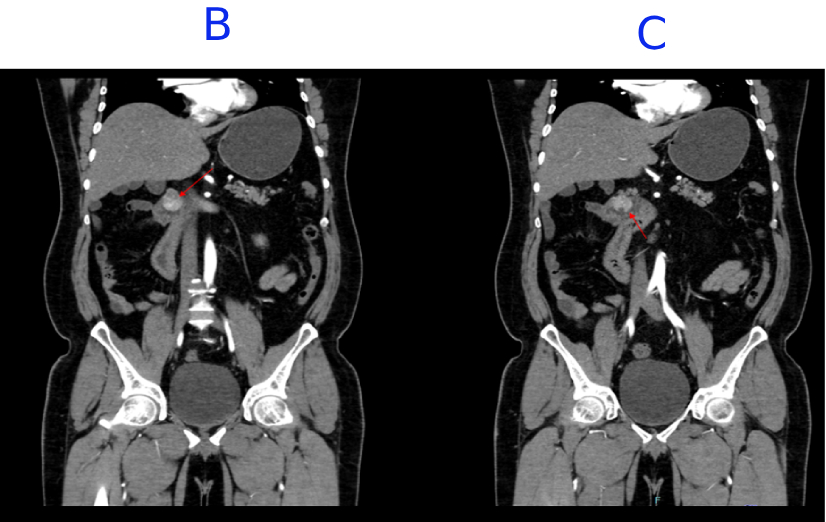

B. Few internal non-enhancing areas are seen in the superior aspect of the lesion.

C. A focal defect seen in the inferior aspect of the lesion, suggestive of ulceration.